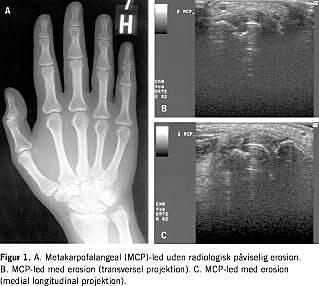

Parallelt med behandlingsforbedringer og tidlig intervention både ved reumatoid artrit (RA) og spondylartropatier (SpA) behøver man nu mere følsomme metoder til diagnostik og kontrol. Stigende evidens peger på, at MR er den nye guldstandard for bedømmelse af perifere og aksiale led ved RA og SpA. UL er mindre valideret, men nye danske resultater har vist, at synovit bedre bedømmes med Doppler-UL end ved klinisk vurdering, og erosioner tidligere påvises med UL end med RTG, måske endda med et forspring på op til to år, sådan som det er set med MR. Forandringer i sene- og kapseltilhæftninger ved SpA kan også erkendes visuelt.